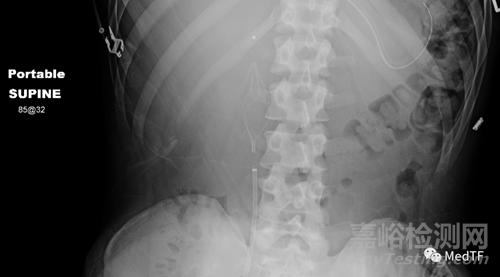

Angel可以放置在床邊,無需將患者轉(zhuǎn)移到導(dǎo)管室內(nèi)治療。放置Angel后,可以通過腹部 X 光片 (KUB) 確認過濾器的正確位置。如果位置不準(zhǔn)確,可以根據(jù)需要重新定位放置過濾器。